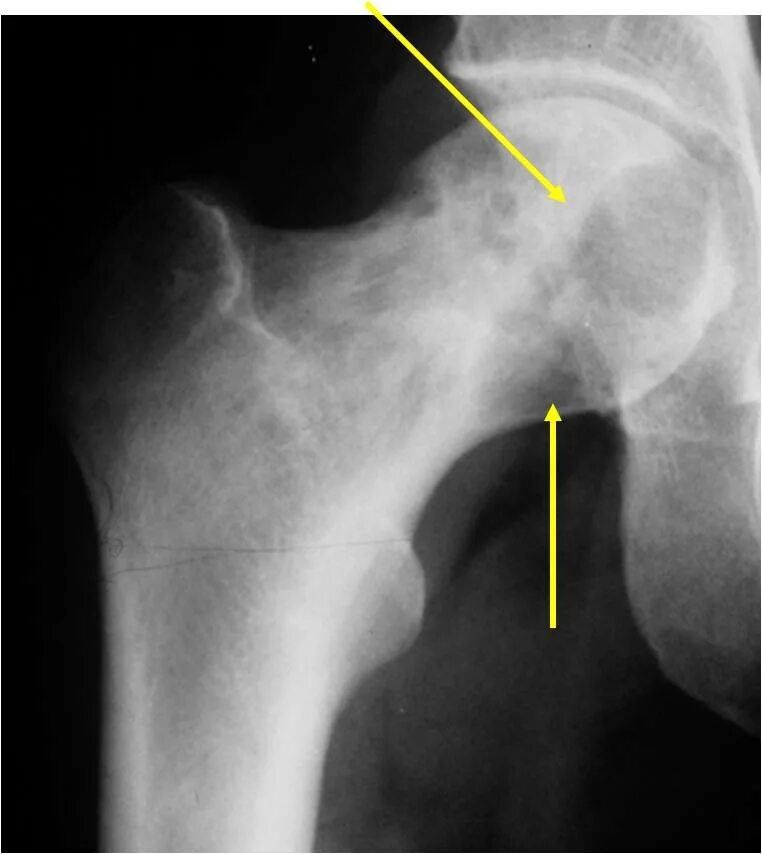

Экзостоз мкб 10